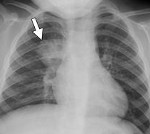

На снимках компьютерной томографии врачи описывают так называемый симптом матового стекла. Это большие участки снижения прозрачности лёгочной ткани, похожие на матовое стекло.

— Что означает появление таких областей?

— Это значит, что в таких местах возникает повреждение на уровне альвеол, отек легких, и эти отделы могут не выполнять функцию насыщения крови кислородом.